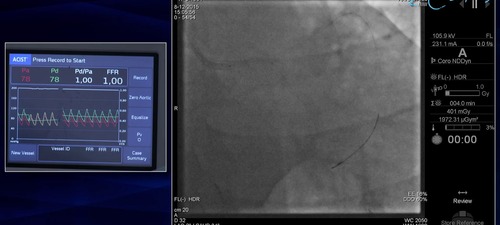

Measurement of FFR in heavily disease side branch

FFR was measured in the circumflex artery using the Navvus micro catheter.  This circumflex artery was particularly challenging as it was heavilty disease and orientated approximately 90o to the left main stem.  After wiring the circumflex artery the Navvus micro catheter is passed into the distal circumflex artery.

• Navigation of 90o bend in a heavilty disease ostial circumflex artery

• Measurement of FFR